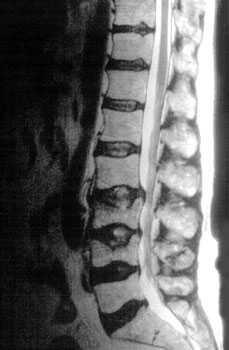

Bone Disease in Multiple Myeloma

Kyle RA. Mayo Clin Proc. 1975;50:29.

• A burdensome and frequent complication in MM

• Present in up to 80% of patients at diagnosis

• Characterized by osteolytic bone lesions secondary to increased bone resorption and impaired bone formation

• Sequelae

• Pathological fractures

• Osteoporosis

• Hypercalcemia

• Bone pain

• Spinal cord compression

MRI Scan

K. Treiti et al. Skeletal Radiology 2021